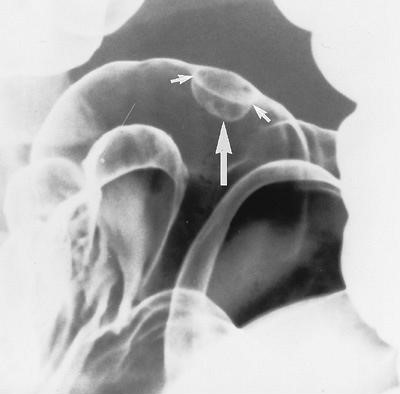

Các polyp lồi từ niêm mạc tạo hình khuyết trong vũng baryt hoặc có viền trắng do baryt phủ và khí – thấu tia x quang bao quanh khi chụp đối quang kép. Các polyp có thể có cuống (Hình 3) hoặc không. Khi nhìn chếch, các polyp có hình “mũ quả dưa”-“bowler hat”(Hình 4).

Hình 4. Dấu hiệu “mũ quả dưa”. Dấu hiệu mũ quả dưa được tạo ra do baryt phủ cả thân polyp (mũi tên lớn) và rãnh (mũi tên nhỏ) giữa đáy của polyp và niêm mạc đại tràng bình thường.